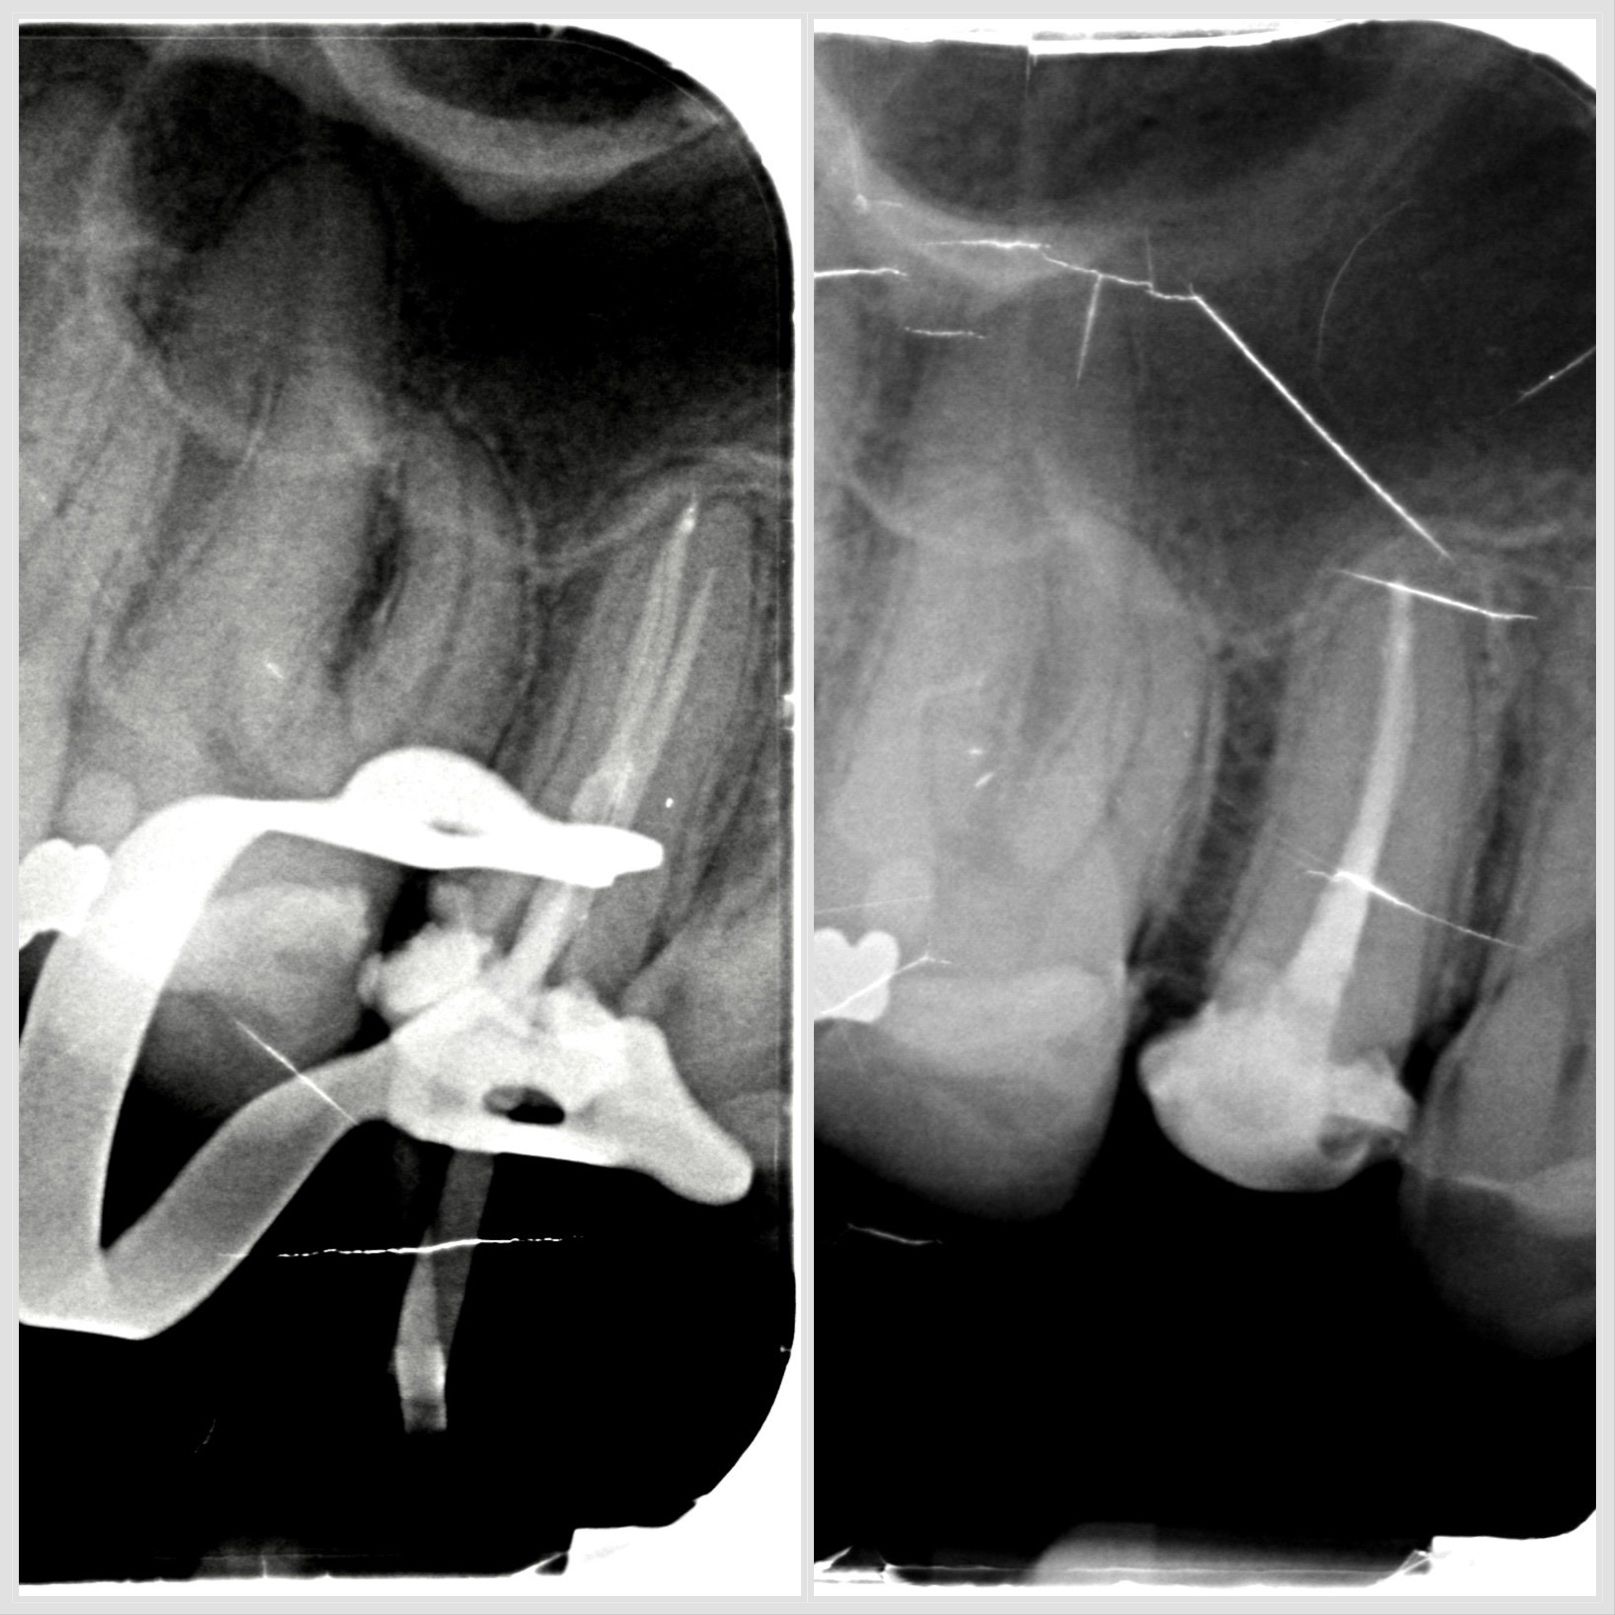

Lésion endo-parodontale sur molaire mandibulaire traitée en endodontie et parodontologie à Apolline Dental Care à Corbeil-Essonnes

Lésion endo-parodontale

#endodontie